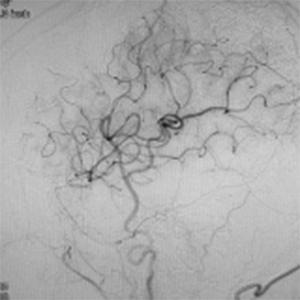

程度が軽い場合には、薬の治療(内科治療)のみを行います。程度が軽い方は、お薬だけで脳梗塞の再発を防げる場合も多いです。しかし、程度がひどい場合、脳血流が低下している場合には、お薬だけでは、2年で20%前後の人が脳梗塞の再発を起こすともいわれております。狭窄や閉塞は慢性的に詰まっており、再開通させることはできません。そのかわりに、頭皮の血管(主に、浅側頭動脈)を剥離し、頭の中の脳血管に顕微鏡を用い吻合することにより、脳の血流量を外から増やすバイパス手術を行います。浅側頭動脈中大脳動脈バイパス術(STAMCAバイパス術)といいます。バイパス術で脳の血流を増やすことにより、脳梗塞の再発する危険性を大きく減らすことできます。現在のガイドラインで推奨されている手術適応は、簡単にいうと73歳以下の比較的元気な方で、脳の血流が著しく低下している方です。最近は、平均寿命も延び、高齢な元気な方も増えております。国内、海外でも高齢者に対するバイパス手術で良好な成績を示す報告は増えております。当院でも、全身状態やほかのご病気の有無を確認し、全身状態が良い場合には、高齢者でも、十分な術前検査を行ったうえで、バイパス手術を行っており、良好な成績を出しております。

また、椎骨動脈や脳底動脈といった後方循環の病変は上記の適応に含まれず、十分なエビデンスがありませんが、内科治療のみでは再発率が高く、特に重篤な脳梗塞をきたすことがわかっております。これらの後方循環の狭窄/閉塞に対するバイパス術を技術的に難しく、成功率を高めるには豊富な経験が必要です。当院では、これらの患者さんに対して十分に精査したうえで、バイパス手術、具体的には、浅側頭動脈上小脳動脈バイパス術(STASCAバイパス術)、後頭動脈後下小脳動脈バイパス術(OAPICAバイパス術)などを行っています。